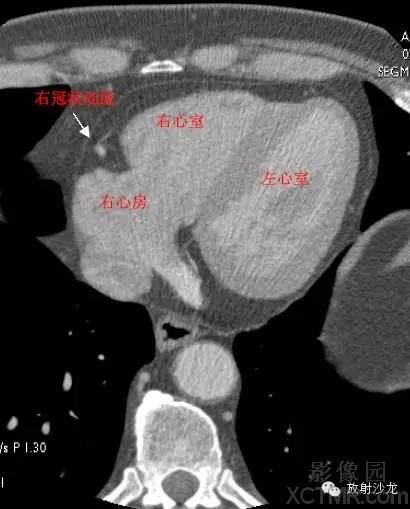

RA -Right Atrium右心房

LV -Left Ventricle左心室

RV -Right Ventricle右心室

RCA -Right Coronary Artery 右冠状动脉